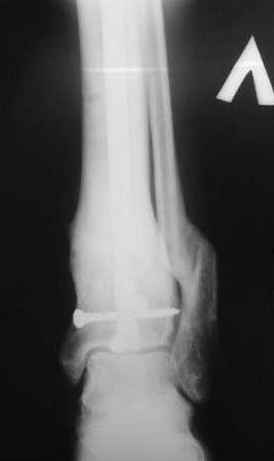

5, 6 - через 2,5 мес после травмы выполнен закрытый остеосинтез блокируемым штифтом.